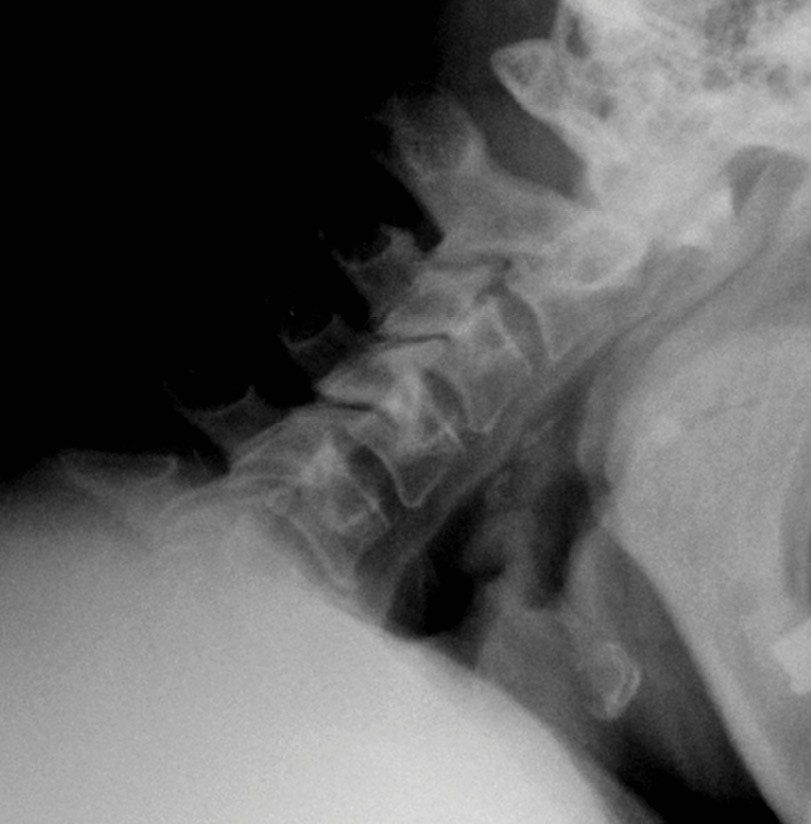

The patient’s symptoms have completely resolved. The x-rays in Figure 8 were taken at the first post-op visit at 2 weeks.